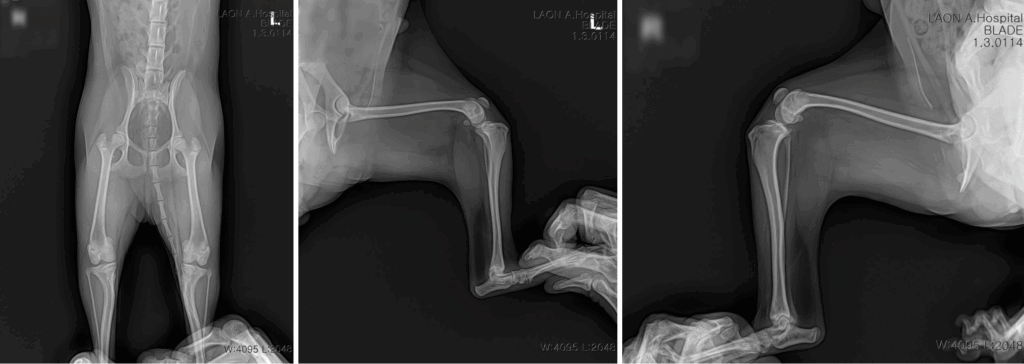

신체검사 및 방사선 촬영을 통해 양쪽 뒷다리 모두 슬개골 탈구 3기(Medial Patellar Luxation Grade 3) 로 확인되었습니다.

무릎뼈가 정상 위치를 벗어나 지속적으로 안쪽으로 빠져 있는 상태로, 관절면 손상과 통증이 동반되어 수술적 교정이 반드시 필요한 상황이었습니다.

수술 전 방사선 검사 결과 / 출처: 라온동물메디컬센터